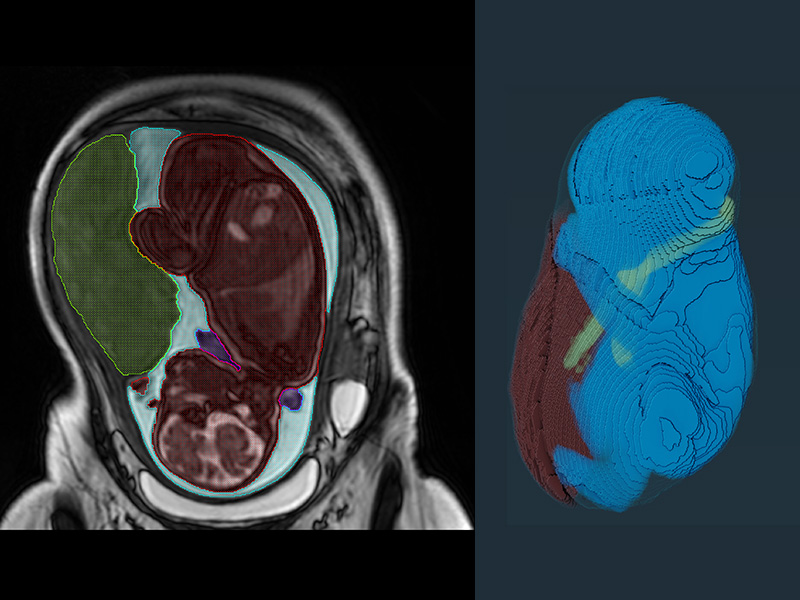

Invasive Placenta Identifcation and Classification

Invasive Placenta Identification and Classification

We are developing machine learning algorithms for detecting and classifying placenta accreta spectrum (PAS) disorder, where the placenta invades the myometrium. This will allow for earlier and more accurate diagnosis, facilitating clinical management and decreasing mortality.